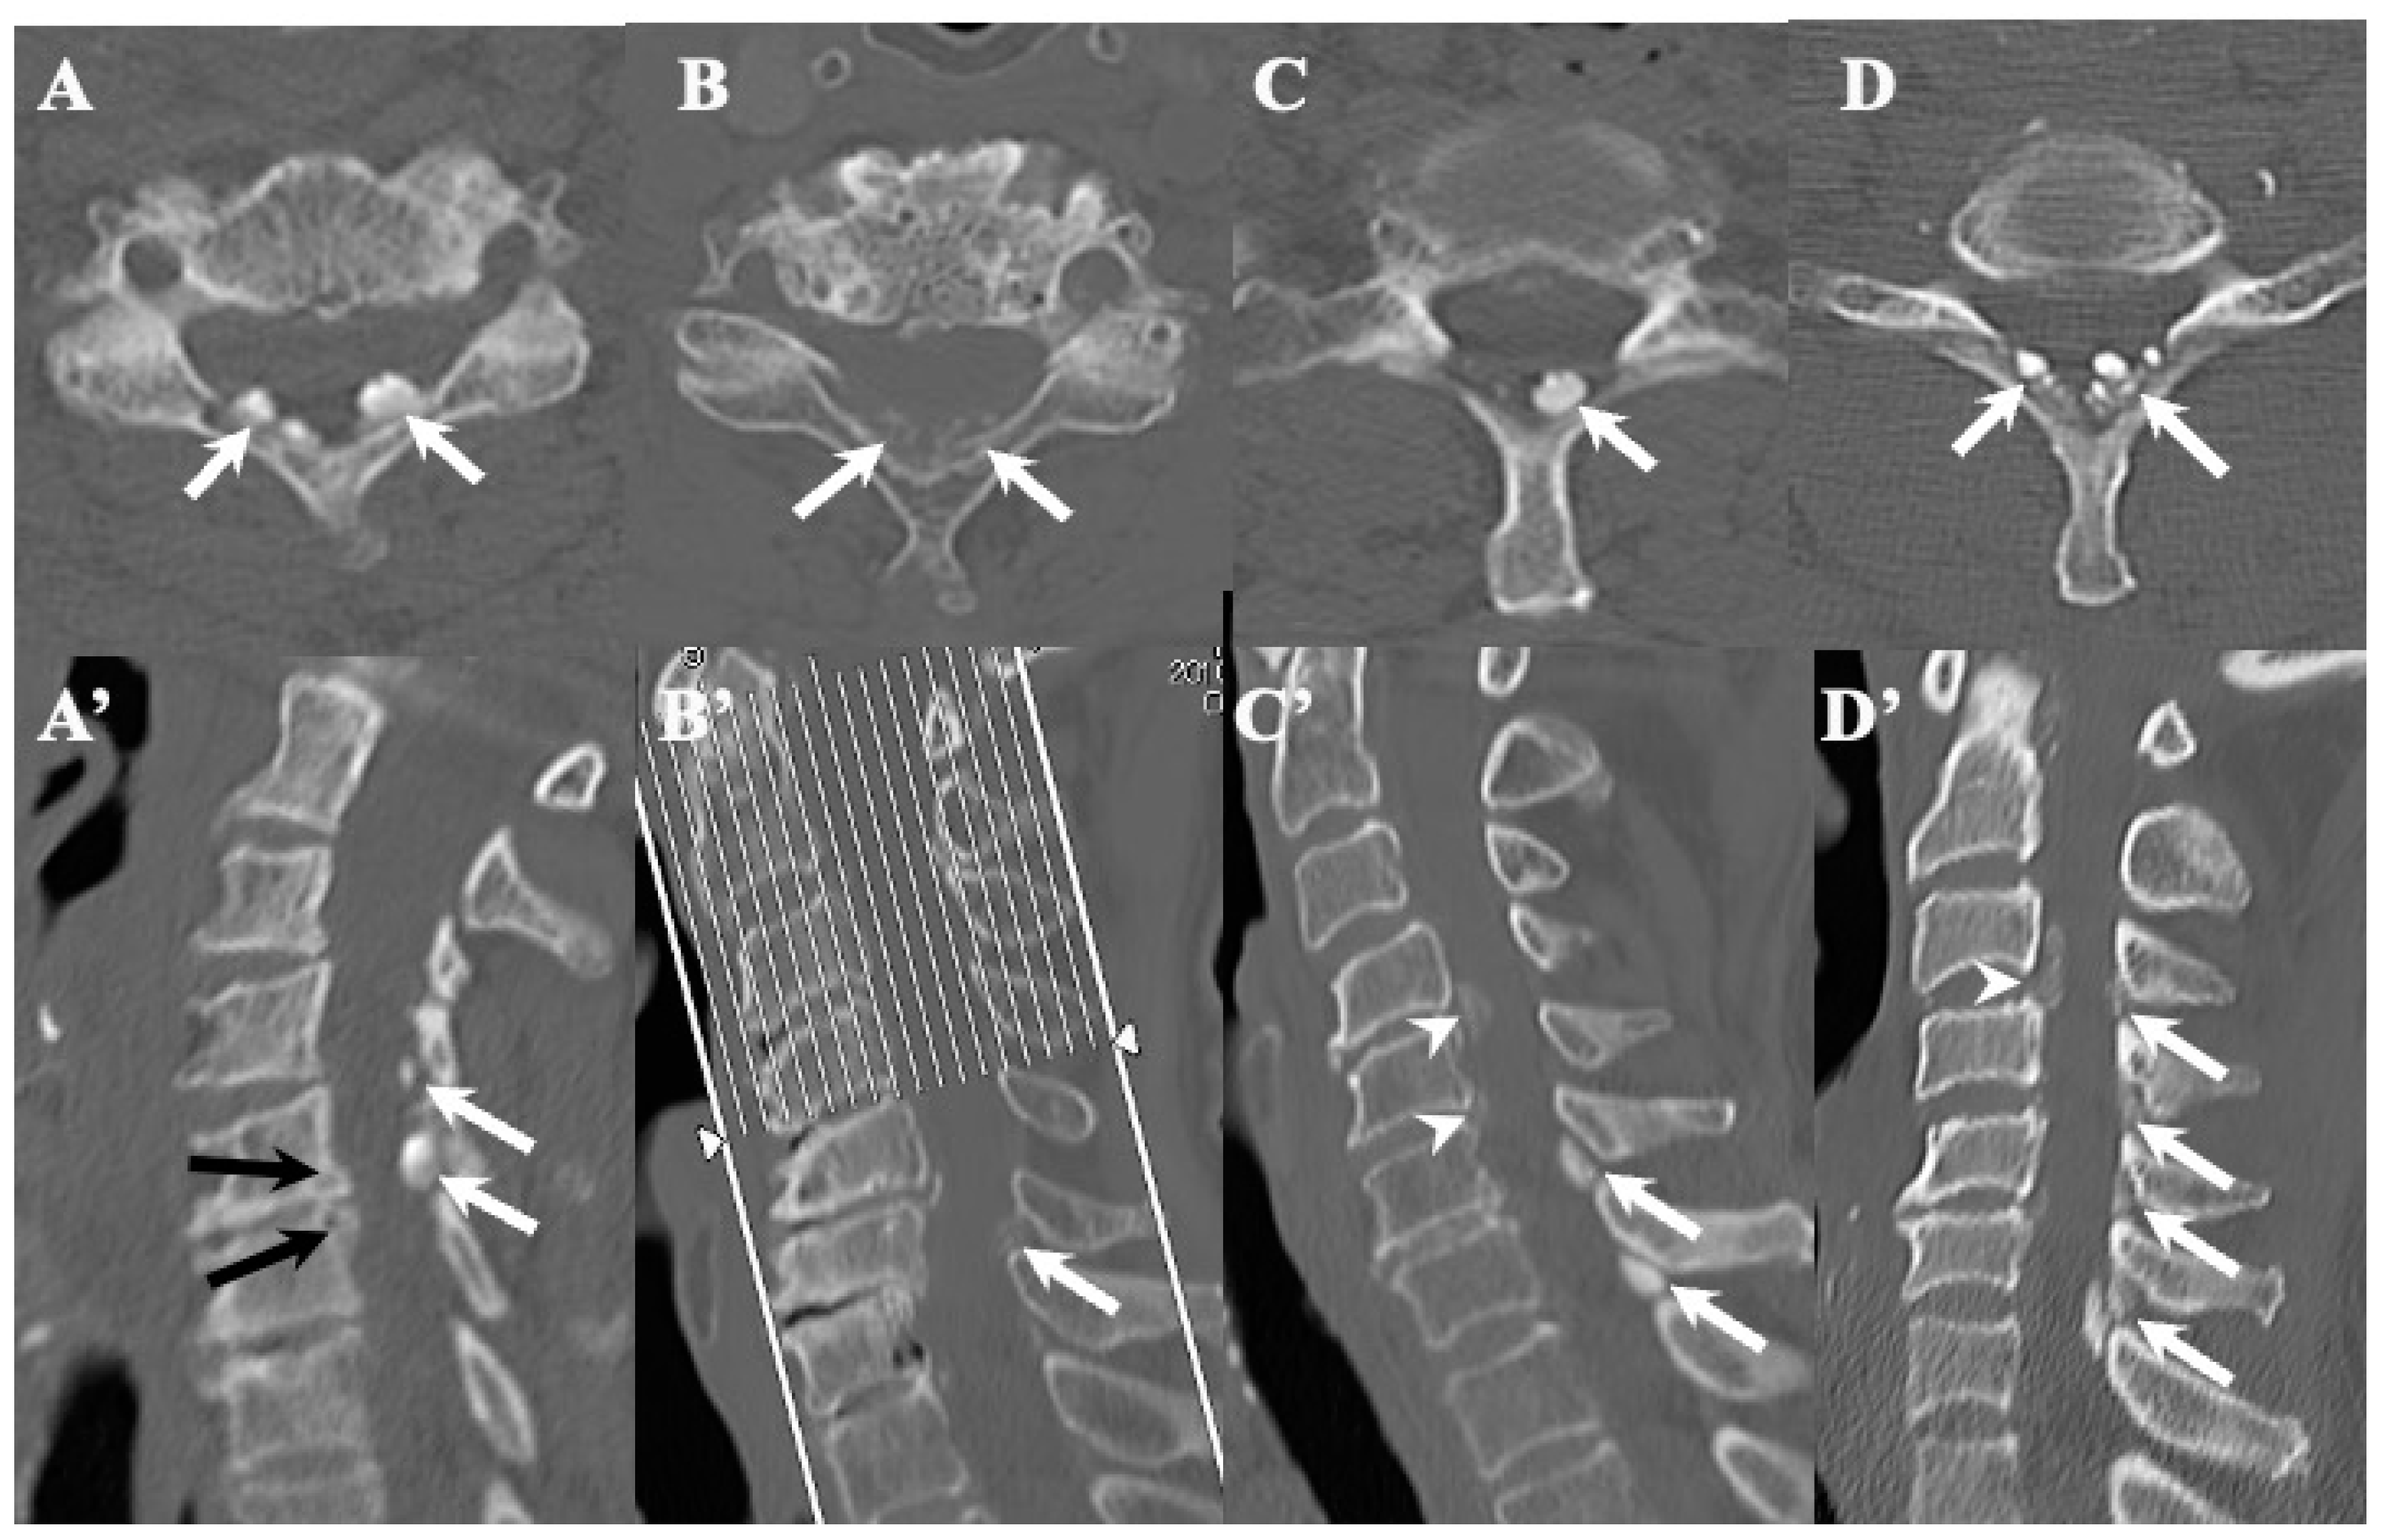

3.3. Neuroradiological Findings (Figure 3, Figure 4, Figure 5 and Figure 6; Table 3)

4.2. Comparison of Neuroradiological Findings between CLF and OLF (Figure 3, Figure 4, Figure 5 and Figure 6; Table 3)